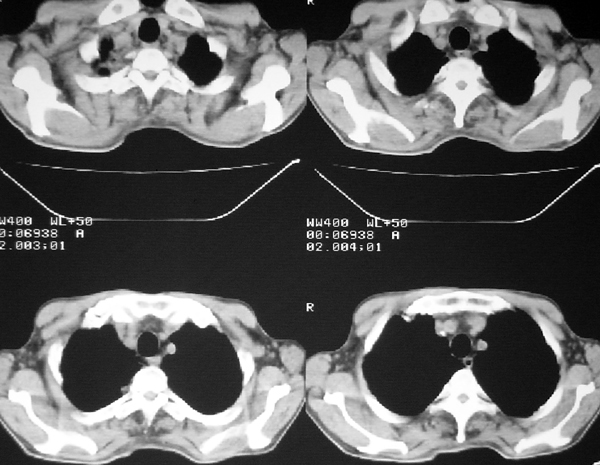

右肺囊实性占位 患者拒绝穿刺活检  近期始终间断性发高烧 使用消炎控制, 左鼻翼部有多发皮肤溃疡

双肺呈毛玻璃状,胸膜旁有多个小囊状气腔。右下囊实性病灶内有园形气体影,边缘光滑,与之相连的胸膜稍增厚,间断发热,抗炎效果不好。考虑机会性感染可能性大。